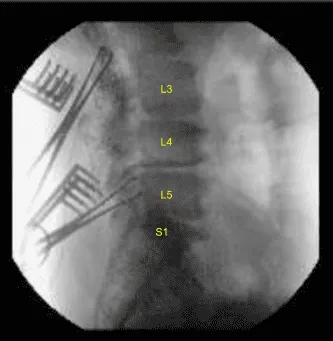

Se realizó una incisión a lo largo de la misma incisión. Con una disección aguda, se podía alcanzar el proceso espinal. Con la disección de Bovie y roma, los procesos espinosos de L2 a S1 quedaron expuestos bilateralmente sobre la articulación facetaria, con la exposición de los TPs en L2, L3, L4, L5 y el ala sacro en ambos lados. Se colocó pinza Allis en las L2 y L5 derechas y se realizó la localización mediante rayos X y se comprobó que estaba en la posición correcta.

Se introdujo la navegación y se realizó una tomografía computarizada. Tras verificar la navegación, se colocaron tornillos pediculares a ambos lados de L2 a S1 secuencialmente bajo guía de navegación tras usar el cambio de marchas, que se golpeaban y comprobaban cada vez con una sonda de punta de bola.